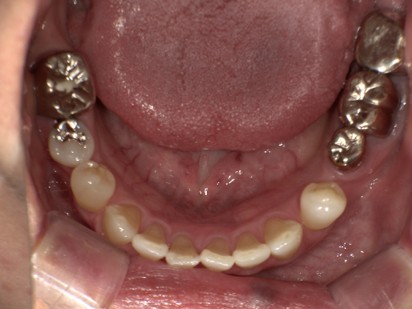

| 主訴 |

インプラント治療の続きをしてほしい。 |

| 治療内容 |

開業前に右下7番と左下7番にインプラント埋入まで行っていた患者様です。インプラント治療の続きを希望されてご来院されました。当院にて二次手術後に上部構造を装着いたしました。元の骨が柔らかく生着まで6ヶ月の待期期間が必要でしたが、現在は問題なく安定しております。 |

| ご来院期間 | 2か月 |

| ご来院回数 | 4回 |

| 治療費用 |

2次手術 5,500×2歯=11,000円 |